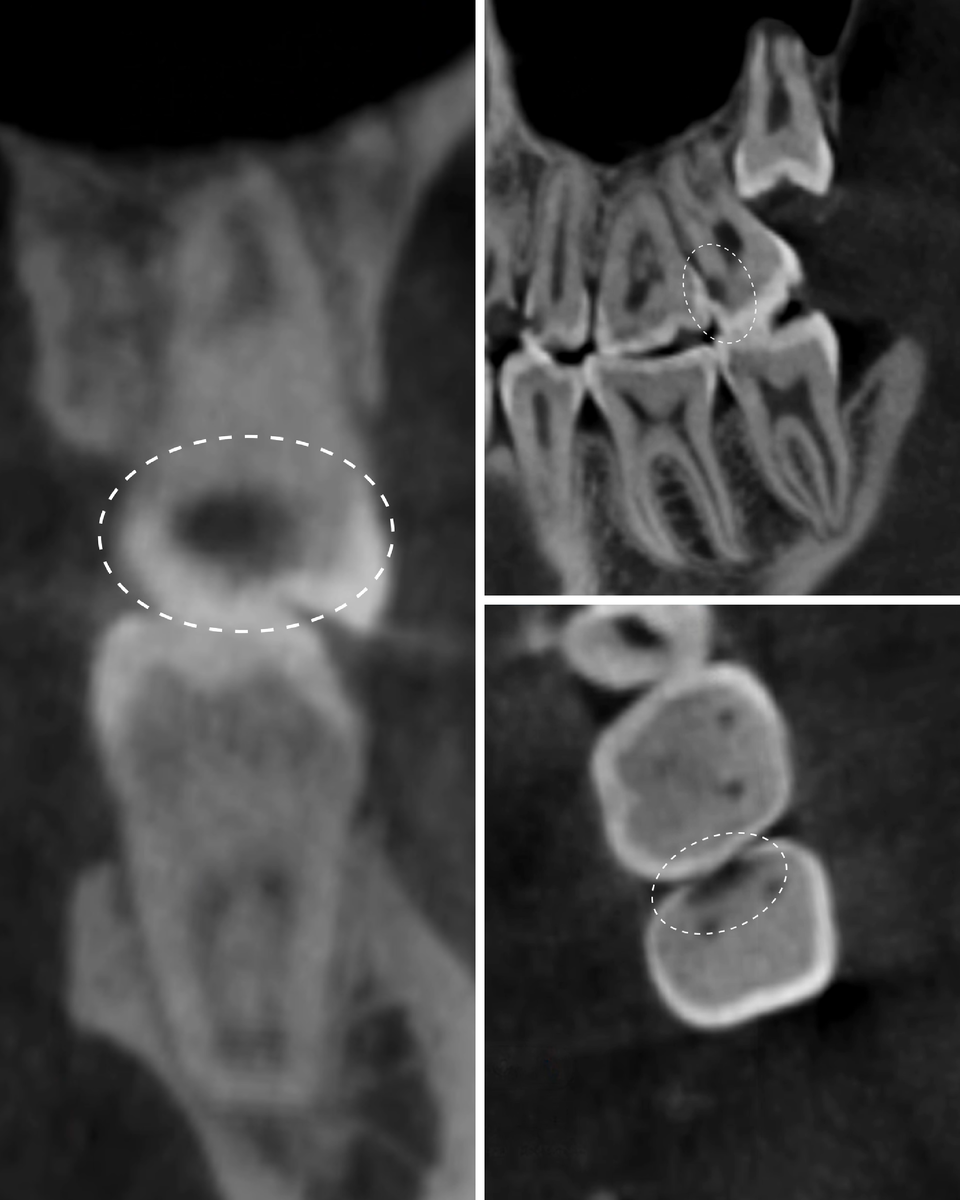

На летнем снимке кариозный процесс выглядел внушительно, но пульпа казалась далеко от полости:

Вроде бы - ничего критичного, можно спокойно лечить и в ус не дуть.

Однако, между летом и зимой прошло много месяцев и кариес почувствовал свою власть, решил отхватить побольше чужих "земель". Вполне успешно, кстати. Но только вскрытие это показало (КТ - низя).

За время, что прошло с момента летнего КТ, кариес разросся, углубился, подобрался вплотную к пульпе, истончив ткани.